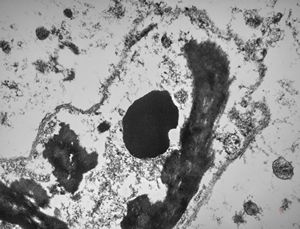

M,6m. | myelinoid inclusions in cerebral neuron - Nieman-Pick disease